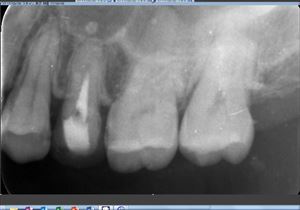

主訴:8年前に治療した歯が違和感、腫れている感じがする。

歯科ドックのCTにこれも病巣が!

左上の5番の根尖に病巣。根管充填が中途半端。根管は狭窄していないようなのになぜ?